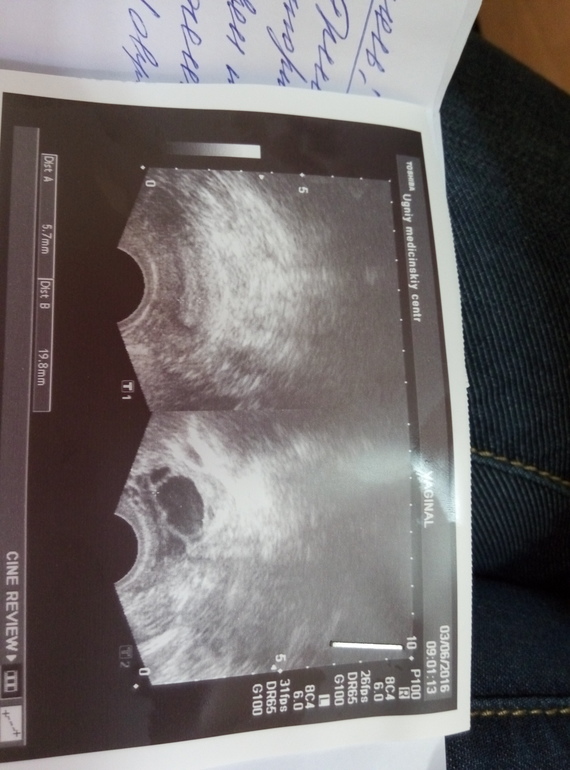

Вчера была на приеме 17 день цикла на узи смотрели фоликулы, пару дней назад он был 13мм, а вчера 19 и какой то такой....

очень похоже на спавшийся фолликул, из которого только вышла як. жидкости нет? надо было колоть укол сразу после узи....